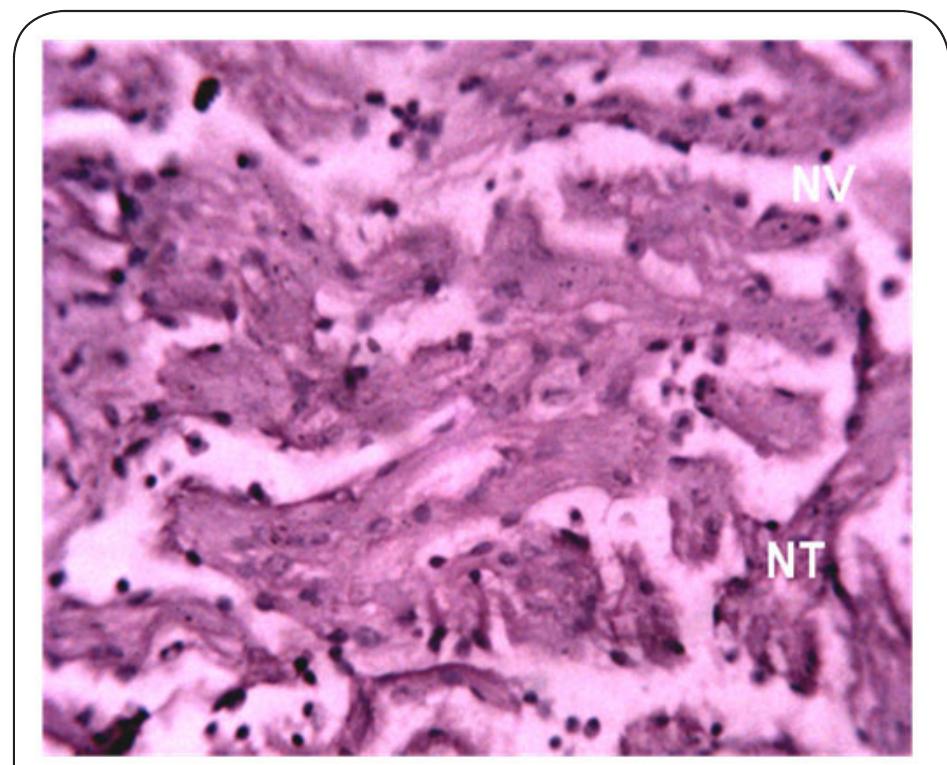

Dr. Ozovehe Patrick Samuel - FEDERAL UNIVERSITY OF TECHNOLOGY, MINNA-NIGERIA